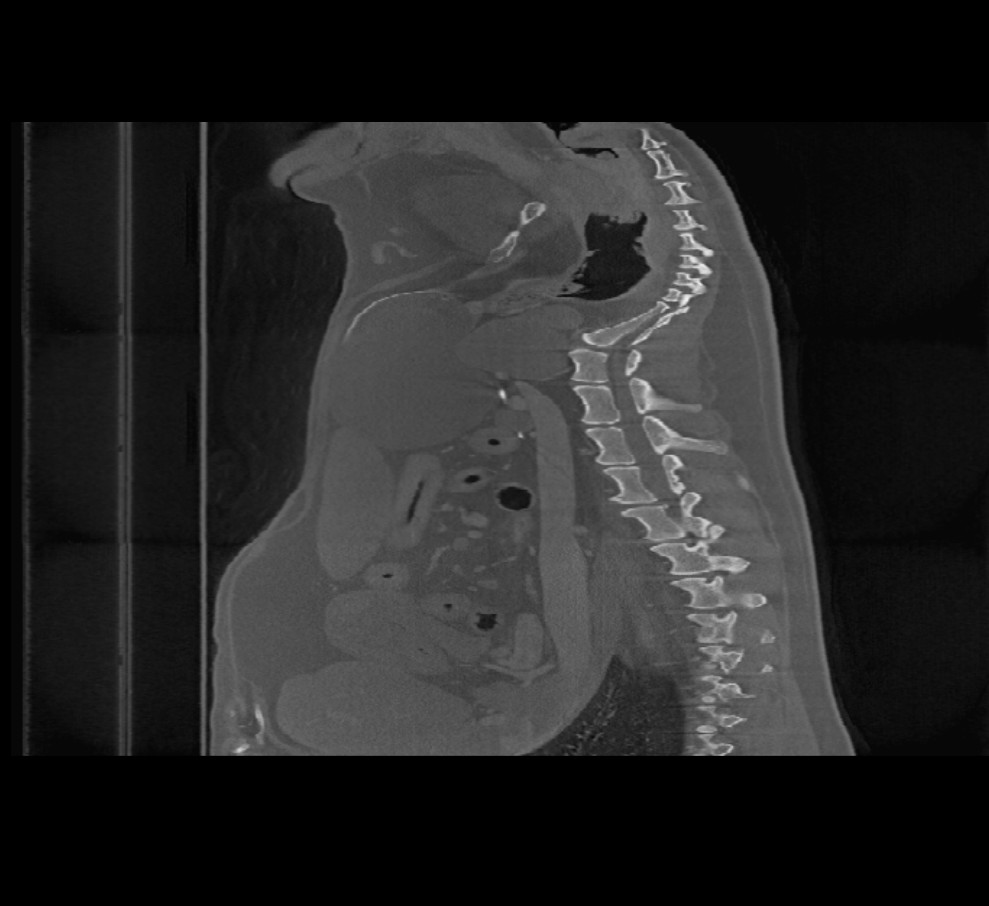

Volumetrikus DICOM képek (CT és MR modalitás) megnyitásakor a Megjelenítő felső eszköztárában egy további menü érhető el (Képsíkok) néven. A kép orientációjának módosításához válassz a három elérhető sík közül: (Axialis, Koronális és Saggitális).

A kiválasztott sík befolyásolja a CT/MR szeletek helyzetét és orientációját, valamint azok 2D síkon történő rekonstrukcióját.